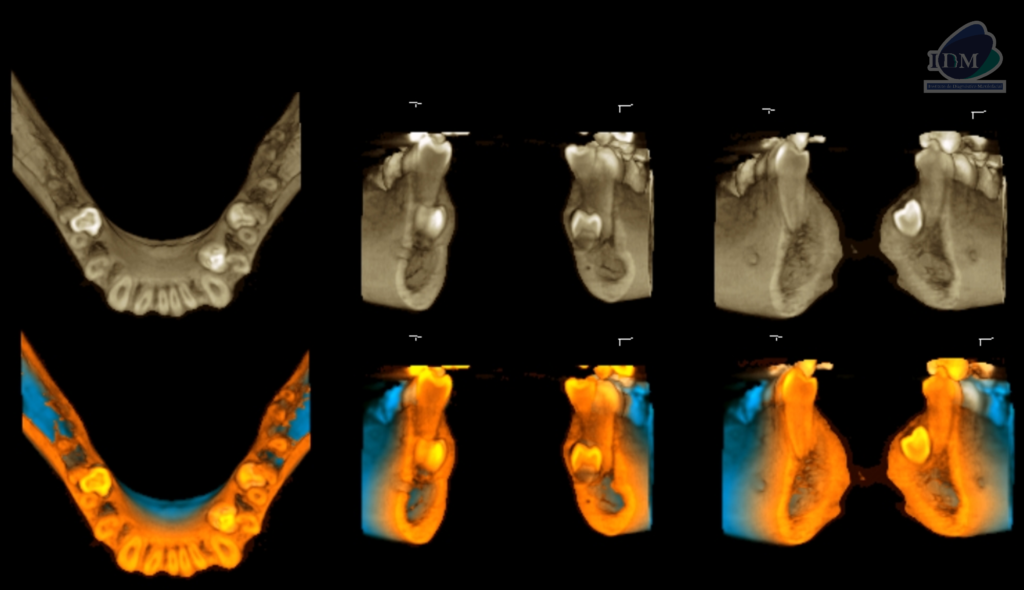

Así mismo en la tomografía volumétrica de haz se evidencia:

- Supernumerario 1: retenida en posición vertical y en contacto con los segmentos radiculares de las piezas 45 y 46, a nivel apical y orientado hacia lingual.

- Supernumerario 2: retenida en posición vertical y en contacto con los segmentos radiculares de las piezas 33 y 34, a nivel apical y orientado hacia lingual.

- Supernumerario 3: retenida en posición vertical y en contacto con los segmentos radiculares de las piezas 35 y 36, a nivel apical y orientado hacia lingual.

RECONSTRUCCIÓN 3D